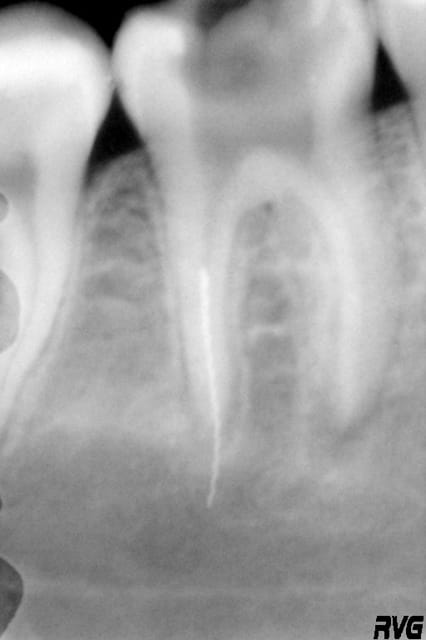

2nde séance : 1h15 a essayer d'aléser autour du rispi pour pouvoir l'attraper grace à un IRS.

3eme : après alésage du tiers coronaire